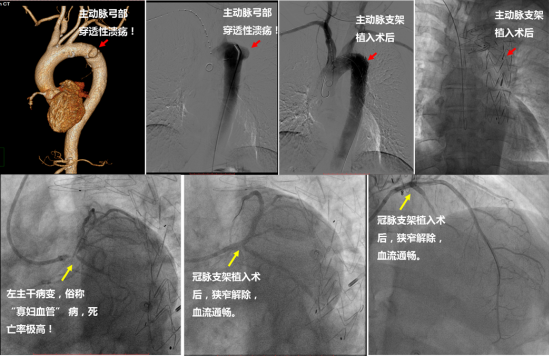

冠脉左主干病变,患者发病即为急性左心衰症状,病情危重,命悬一线,随时有猝死、心源性休克、再次心梗等风险。科室经过详细术前讨论,拟行主动脉内球囊反搏(IABP)支持下的冠脉左主干病变介入治疗手术,解决患者危急情况。然而屋漏偏逢连夜雨,郭宁主任医师及罗永百主治医师在仔细查阅患者当地资料时发现,外院胸部 CT 提示胸主动脉溃疡可能。心内科紧急安排了急诊胸主动脉 CT 血管造影检查,结果回报:主动脉弓部囊状突起,考虑穿透性溃疡。胸主动脉溃疡也是胸痛急症,病情凶险,一旦溃疡穿透主动脉壁,可能造成主动脉夹层、猝死等危急情况,且主动脉溃疡为主动脉内球囊反博术禁忌,增加了冠脉支架手术风险,这一结果让患者本就凶险的病情雪上加霜。

心内科郭宁主任医师团队反复评估患者病情,邀请周围血管科田红燕主任医师、张军波副主任医师联合会诊后,决定实施「一站式血管治疗」手术,即先由周围血管科行主动脉腔内隔绝术,再同期由心内科在 IABP 支持下行冠状介入术,必要时联合心外科给予 ECMO 支持。

6 月 11 日一早,田红燕主任医师、张军波副主任医师首先成功为患者实施了主动脉腔内隔绝术。之后郭宁主任医师、罗永百和张勇主治医师顺利置入 IABP,并干预复杂左主干病变,术中患者生命体征平稳,术后造影结果满意,整体左冠脉严重狭窄解除,血流恢复正常。经过 3 个多小时的努力,顺利结束手术返回病房,并于 2 天后出院。